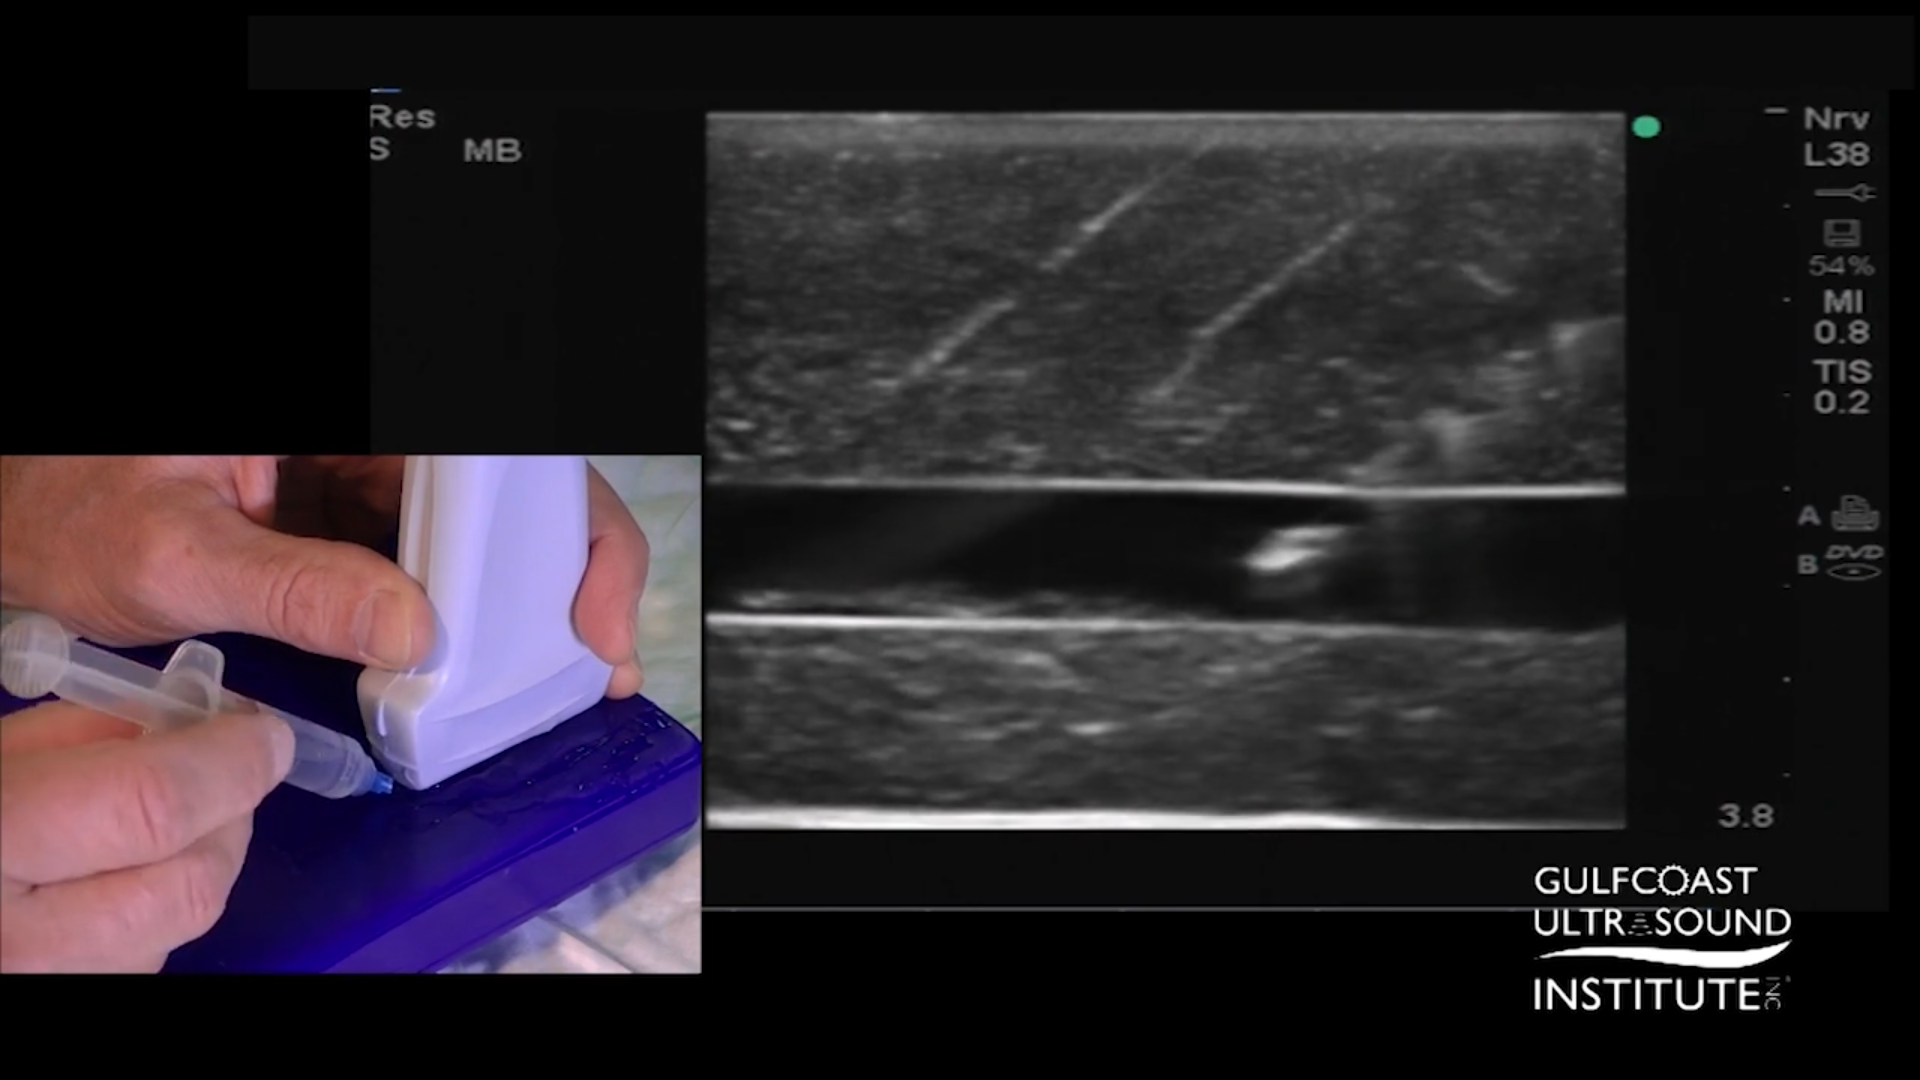

- Refine with a Shallower Angle for Precision:

Once in proximity to the target, try lowering the angle to around 15 degrees. This shallower angle offers finer control as you make the final approach. The side-to-side fanning technique remains useful at this stage, helping keep the needle tip centered and bright in the imaging plane. Continue advancing only when the tip is at its brightest, indicating that it’s centered within the plane.